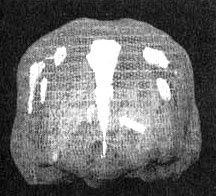

Иллюстрация к книге — Измените свой мозг - изменится и жизнь! [i_056.jpg]

Трехмерное изображение — активный мозг